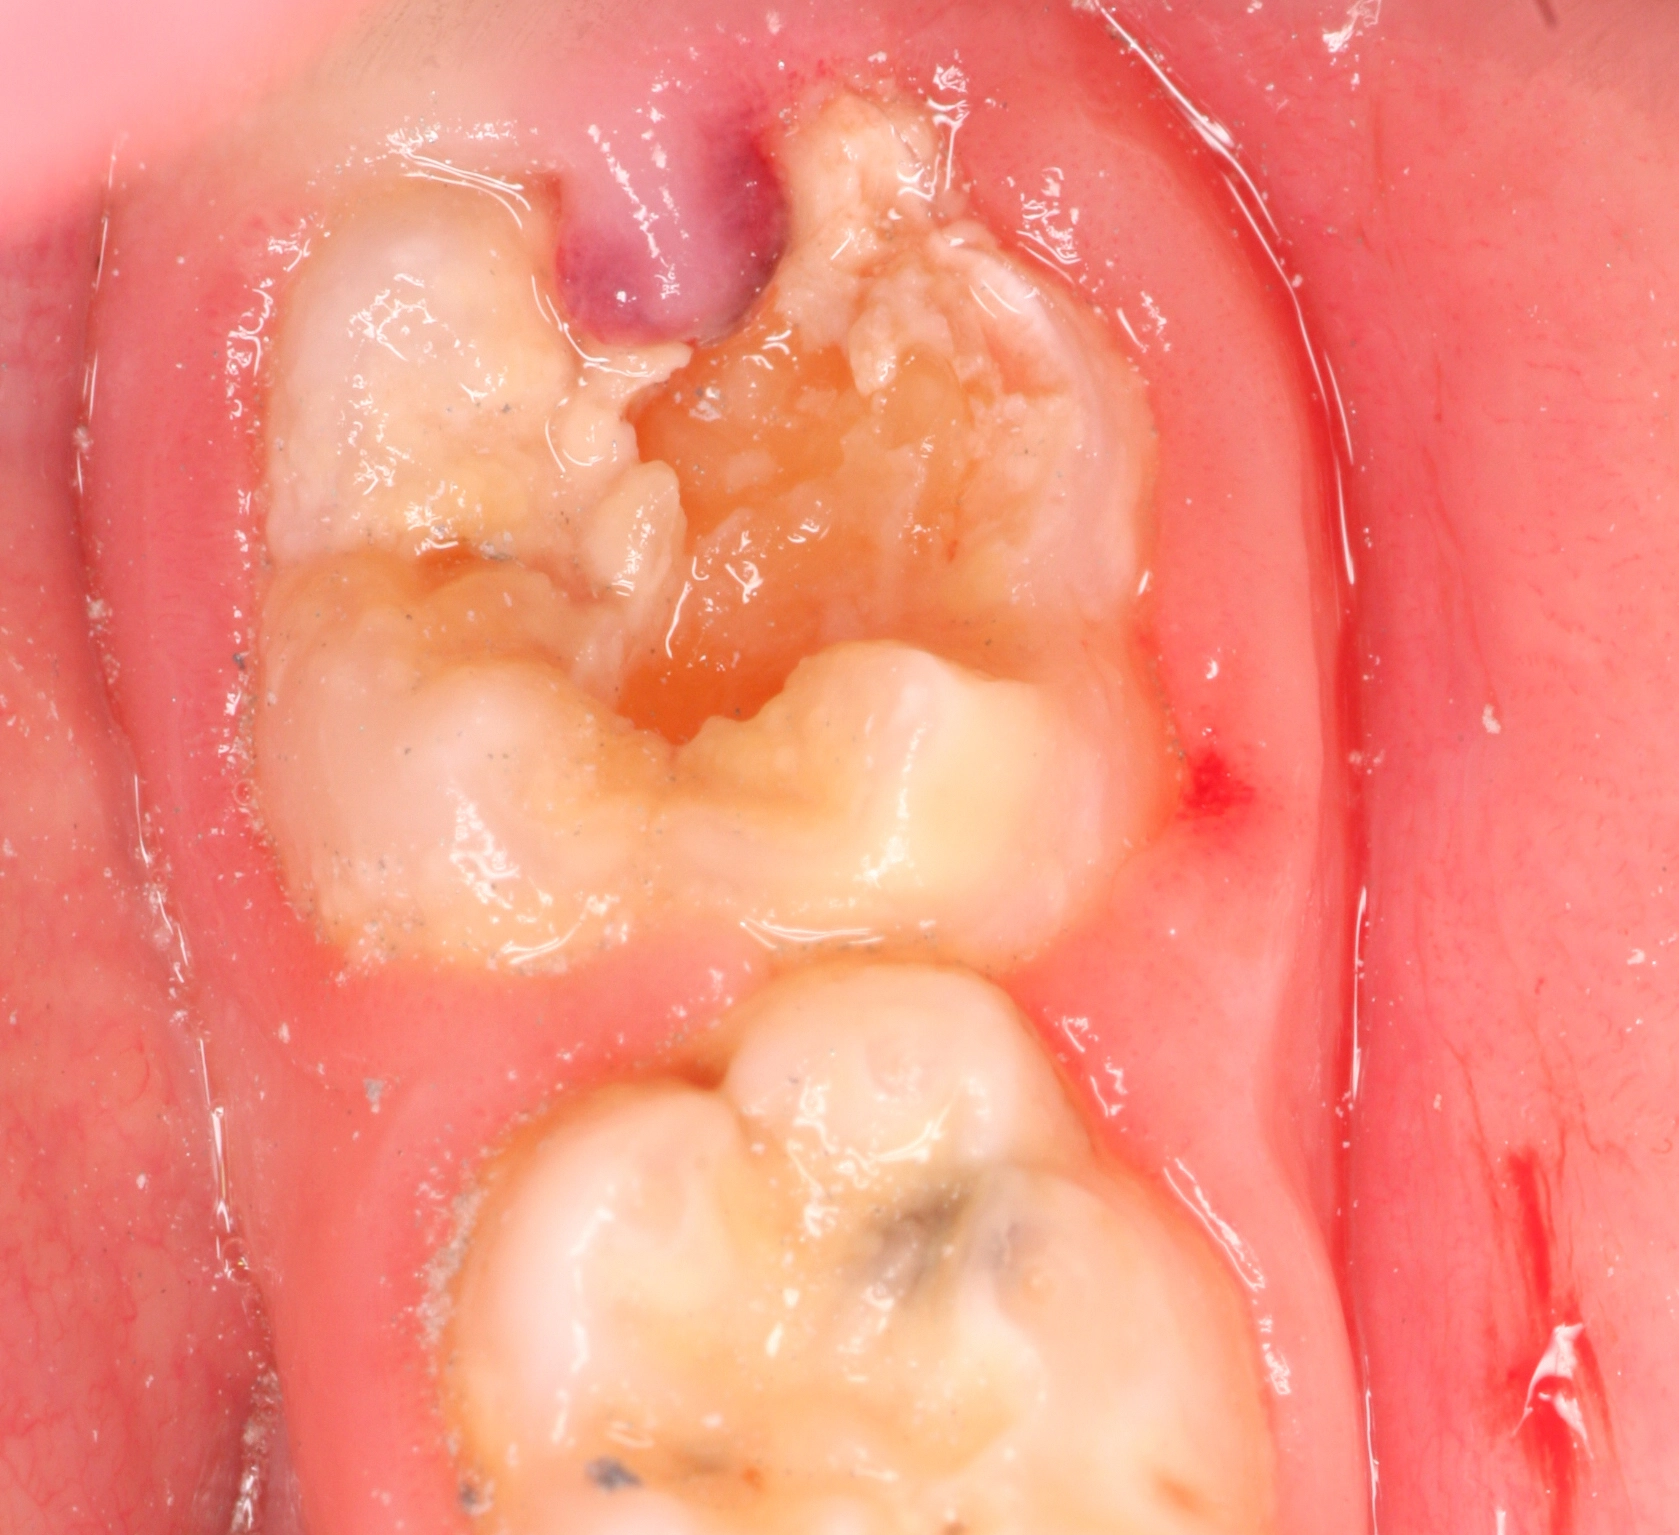

- Grad III: große gelblich-braune Areale im gesamten Zahnbereich mit Defekten in der Kronenmorphologie und starken Schmelzverlusten, gekoppelt mit einer hohen Empfindlichkeit der Zähne (Abb. 4)

Je nach Schweregrad der Hypomineralisation erstreckt sich die zu favorisierende Therapie von der Intensivprophylaxe bis hin zu restaurativen Maßnahmen oder sogar der Extraktion. Von MIH betroffene Frontzähne stellen meist aufgrund des geringeren Ausprägungsgrades der Hypomineralisation vor allem ein ästhetisches Problem dar [22]. Im Gegensatz dazu führt die MIH im Molarenbereich durch die mastikatorisch-funktionelle Belastung meist zu posteruptiven Schmelzabbrüchen mit konsekutiver Exposition des Dentins (insbesondere im Bereich der Höckerspitzen) [1] und erfordert ein schnelles Eingreifen. Unabhängig vom vorliegenden Schweregrad der MIH sollten alle betroffenen Kinder engmaschig in einem Intensivprophylaxe-Programm betreut werden. Hierzu werden folgende Maßnahmen empfohlen: regelmäßige Zahnreinigungen mit Mundhygieneanleitungen sowie die Applikation von Fluorid-, CHX- und CPP-ACP-Präparaten [18].

Für die Restauration hypomineralisierter Zähne stehen verschiedene Möglichkeiten zur Auswahl, die von verschiedenen Faktoren abhängig sind: dem Alter der Patienten, der Ausdehnung und Qualität (Härte) der Zahnhartsubstanz, dem Schweregrad, dem Ausmaß der Empfindlichkeit und der Lokalisation der betroffenen Zähne. Sie alle nehmen Einfluss auf das zu verwendende Material [22]. Bei leichten bis mittleren Defekten ist Komposit ein gutes Therapiemedium (Abb. 5). Kompositfüllungen zeigen bei adäquater Verarbeitung eine gute Überlebensrate [23]. Die Füllungsränder sollten komplett im gesunden Schmelz liegen, da sonst die Gefahr eines weiteren Zahnsubstanzverlustes besteht [23]. Für die Erstversorgung von Zähnen, bei denen aufgrund des noch unvollständigen Zahndurchbruchs keine absolute Trockenlegung möglich ist, eignen sich Glasionomerzemente, die dann aber langfristig durch definitive Füllungen ausgetauscht werden sollten [24].

Bei größerem Substanzverlust und massiven Hypersensibilitäten kann zum Erhalt betroffener Molaren als Therapieoption die Eingliederung einer konfektionierten Stahlkrone als Langzeitprovisorium gewählt werden [25]. Neuere Therapieansätze propagieren neben der Stahlkrone den Einsatz laborgefertigter Arbeiten aus Komposit [26]. Diese weisen den Vorteil auf, dass defektbezogen versorgt werden kann und es somit zu einem maximalen Schutz der nicht betroffenen Zahnhartsubstanz kommt. Das Material Komposit hat gegenüber der Keramik den Nutzen, dass es in dünneren Schichtstärken verwendet und ebenso ohne Schwierigkeiten in die kieferorthopädische Behandlung einbezogen werden kann. So ist beispielsweise das Befestigen eines Tubes auf Komposit deutlich einfacher durchzuführen als auf Keramik.

Bei starker kariöser Zerstörung des MIH-Zahnes sowie ausgeprägten Substanzverlusten der ganzen Zahnkrone und/oder endodontischen Problemen kann als Therapieoption auch die Extraktion der befallenen Molaren in Betracht gezogen werden. Diese Frage nach der Erhaltungswürdigkeit und Prognose des Zahnes sollte aber in jedem Fall mit einem Kieferorthopäden vor Behandlungsbeginn abgeklärt werden [27, 28]. Eine strukturierte Zusammenfassung des Therapieplans basierend auf dem MIH-TNI wurde vor Kurzem in der Zeitschrift „Oralprophylaxe und Kinderzahnheilkunde“ veröffentlicht [20, 21].